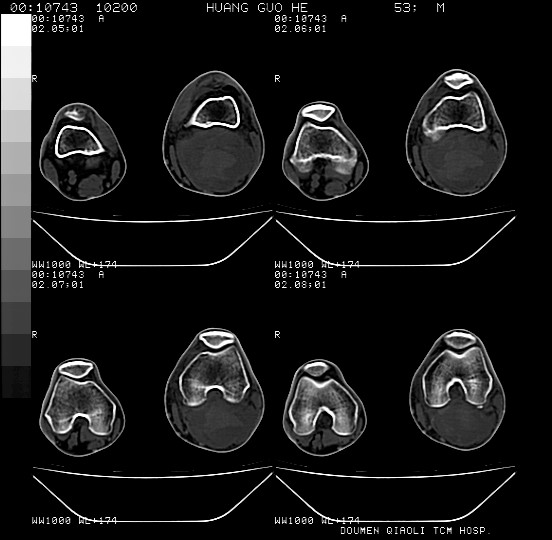

男性,左腘窝包块五个月,逐渐增大,疼痛功能受限,无发热。

查:远端血供差,质地硬。

左侧膝关节后国窝处略低密度软组织肿块,边界清楚,内见脂肪密度及高密度影.多考虑:软组织肿瘤_首选:脂肪纤维瘤.

左侧腘窝软组织肿块,边缘清晰,其内密度不均,周围骨组织无破坏,病灶增长较快,考虑:恶性病变(腘窝滑膜肉瘤可能),建议穿刺活检。